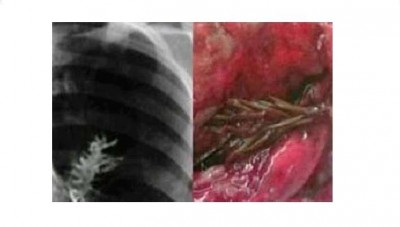

ابتلع بذرة ... فأنبتت في رئته " شاهد الصور"

أصيب أطباء روس بالذهول خلال إجراء فحوص لرجل من منطقة الأورال الروسية كان يشكو من ألم حاد في صدره وسعال شديد مصحوب بدم بعد رؤيتهم نبتة داخل إحدى رئتيه طولها نحو خمسة سنتيمترات من شجرة التنوب.

وتوقع الأطباء قبل إجراء الفحوص أنه مصاب بورم في الرئة لكنهم وجدوا هذه النبتة, وقد قام الأطباء باستصال الرئة بالكامل لأنه يصعب إخراج النبته بدون تضرر الرئة.

وتفسير ذلك أن النبته انتقلت للجهاز التنفسي بدلاً من الجهاز الهضمي ونمت في الرئة.